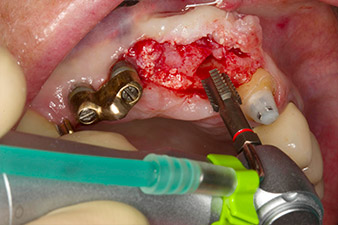

Motorized placement of the implant

Fig. 4: Motorized placement of the implant with the WS-75 L contra-angle handpiece at a ratio of 20:1 (programme P5).

In order to compensate for the periodontal bone loss and achieve an aesthetically pleasing result, the implantation was combined with guided bone regeneration (GBR) with xenogenic replacement material and a collagen membrane

(Fig. 5 and 6).

Xenogenic bone substitute material

Fig. 5: In order to achieve the best possible quality of peri-implant tissue, the site was additionally augmented with xenogenic bone replacement material and a collagen membrane in the scope of guided bone regeneration.